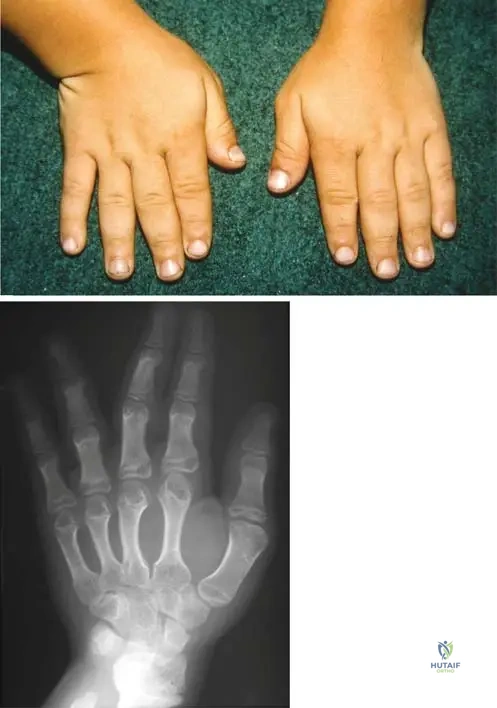

A 7-year-old girl presents with multiple bony deformities and leg length discrepancy. Radiographs show numerous enchondromas affecting multiple bones, particularly in the lower extremities, leading to significant skeletal asymmetry. This constellation of findings is most consistent with which condition?

Correct Answer: C

Rationale: The clinical context for Fig. 8.22 a, b explicitly links "Short stature and osseous deformity secondary to Ollier’s disease" with multiple enchondromas. Ollier's disease is characterized by multiple enchondromas, often unilateral, leading to significant skeletal deformities and growth disturbances. The other conditions are distinct skeletal dysplasias or disorders not primarily characterized by multiple enchondromas.

A 9-year-old boy presents with progressive bowing of his right leg and a noticeable limb length discrepancy. Radiographs reveal multiple enchondromas predominantly affecting the bones of the right lower extremity, leading to significant osseous deformities. This condition is best described as:

View Answer & Explanation

Rationale: The clinical context for Fig. 8.22 a, b explicitly states "Short stature and osseous deformity secondary to Ollier’s disease." Ollier's disease is characterized by multiple enchondromas, often unilateral, leading to significant skeletal deformities and growth disturbances. Solitary enchondroma does not involve multiple lesions. Maffucci syndrome includes hemangiomas, not mentioned. Chondrosarcoma is malignant. Fibrous dysplasia is a different bone disorder.

A 9-year-old boy presents with progressive bowing of his left forearm and shortening of his left leg. Physical examination reveals multiple palpable bony masses in the metaphyses of the long bones of the left upper and lower extremities. Radiographs show numerous lucent lesions with punctate calcifications, consistent with enchondromas, predominantly affecting the left side of his body. There are no associated soft tissue hemangiomas.

Rationale: The presence of multiple enchondromas, often unilateral or asymmetric, leading to skeletal deformities and limb length discrepancies, without associated soft tissue hemangiomas, is characteristic of Ollier's Disease (enchondromatosis). Maffucci Syndrome is similar but includes soft tissue hemangiomas. Multiple Hereditary Exostoses involves osteochondromas (exostoses), not enchondromas. Fibrous dysplasia has a "ground-glass" appearance. Chondrosarcoma is a malignant tumor, though it can arise from enchondromas, the primary diagnosis here is the underlying syndrome.

A 9-year-old girl presents with progressive bowing of her left forearm and shortening of her left leg. Physical examination reveals multiple firm, non-tender masses palpable along the metaphyses of the long bones in her left upper and lower extremities. Radiographs show multiple radiolucent lesions with punctate calcifications, consistent with enchondromas, predominantly affecting one side of her body.

Rationale: The presence of multiple enchondromas, often unilateral or asymmetric, leading to limb length discrepancies and deformities, is characteristic of Ollier's disease (enchondromatosis). Maffucci syndrome is Ollier's disease combined with soft tissue hemangiomas. Multiple hereditary exostoses involve osteochondromas, not enchondromas. Fibrous dysplasia has a different radiographic appearance (ground-glass). Osteochondromatosis is a less specific term, often referring to MHE.